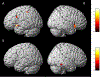

Results: The cancer group showed regional reductions over 12 months in frontal, temporal, and parietal gray matter on VBM, reduced FreeSurfer cortical thickness in prefrontal, parietal, and insular regions, and increased working memory-related fMRI activation in frontal, cingulate, and visual association cortex. Controls showed only reductions in fusiform gyrus on VBM and FreeSurfer temporal and parietal cortex thickness. Women with breast cancer showed higher estimated brain age and lower regional gray matter volume than controls at both time points. The cancer group showed a trend toward lower performance in attention, processing speed, and executive function at follow-up. There were no significant associations between brain imaging metrics and cognition or days on hormonal therapy.